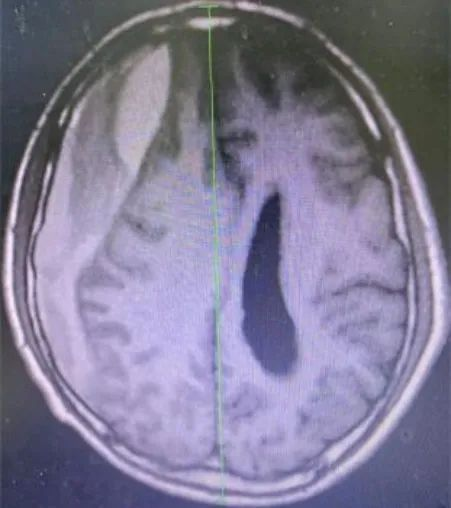

术前

附二医院副院长赵正据了解情况后将患者收治到外一科,管床医生张胜伟详细查体及询问病史后,完善头部CT、MRI等检查,推翻了之前“颈椎病”的诊断,更改诊断为“亚急性硬膜下血肿伴脑疝形成”。赵正据教授考虑到患者年龄大,基础疾病多,病情紧急,迅速组织医生急诊采用微创技术为患者进行治疗。术中,张胜伟医生精细操作,手术切口长度仅4cm,术中出血不到10ml,手术时长不到1小时。护理团体严密观察术后患者的生命体征、意识、肌力、肢体感觉等,做好引流管的护理及相关健康知识宣教。术后患者言语清晰,肢体活动正常,动态复查头颅CT显示颅内血肿清除效果良好,术后1周即顺利出院。患者为表示感谢,特为科室医护送上“医术精湛,尽职尽责”的锦旗。